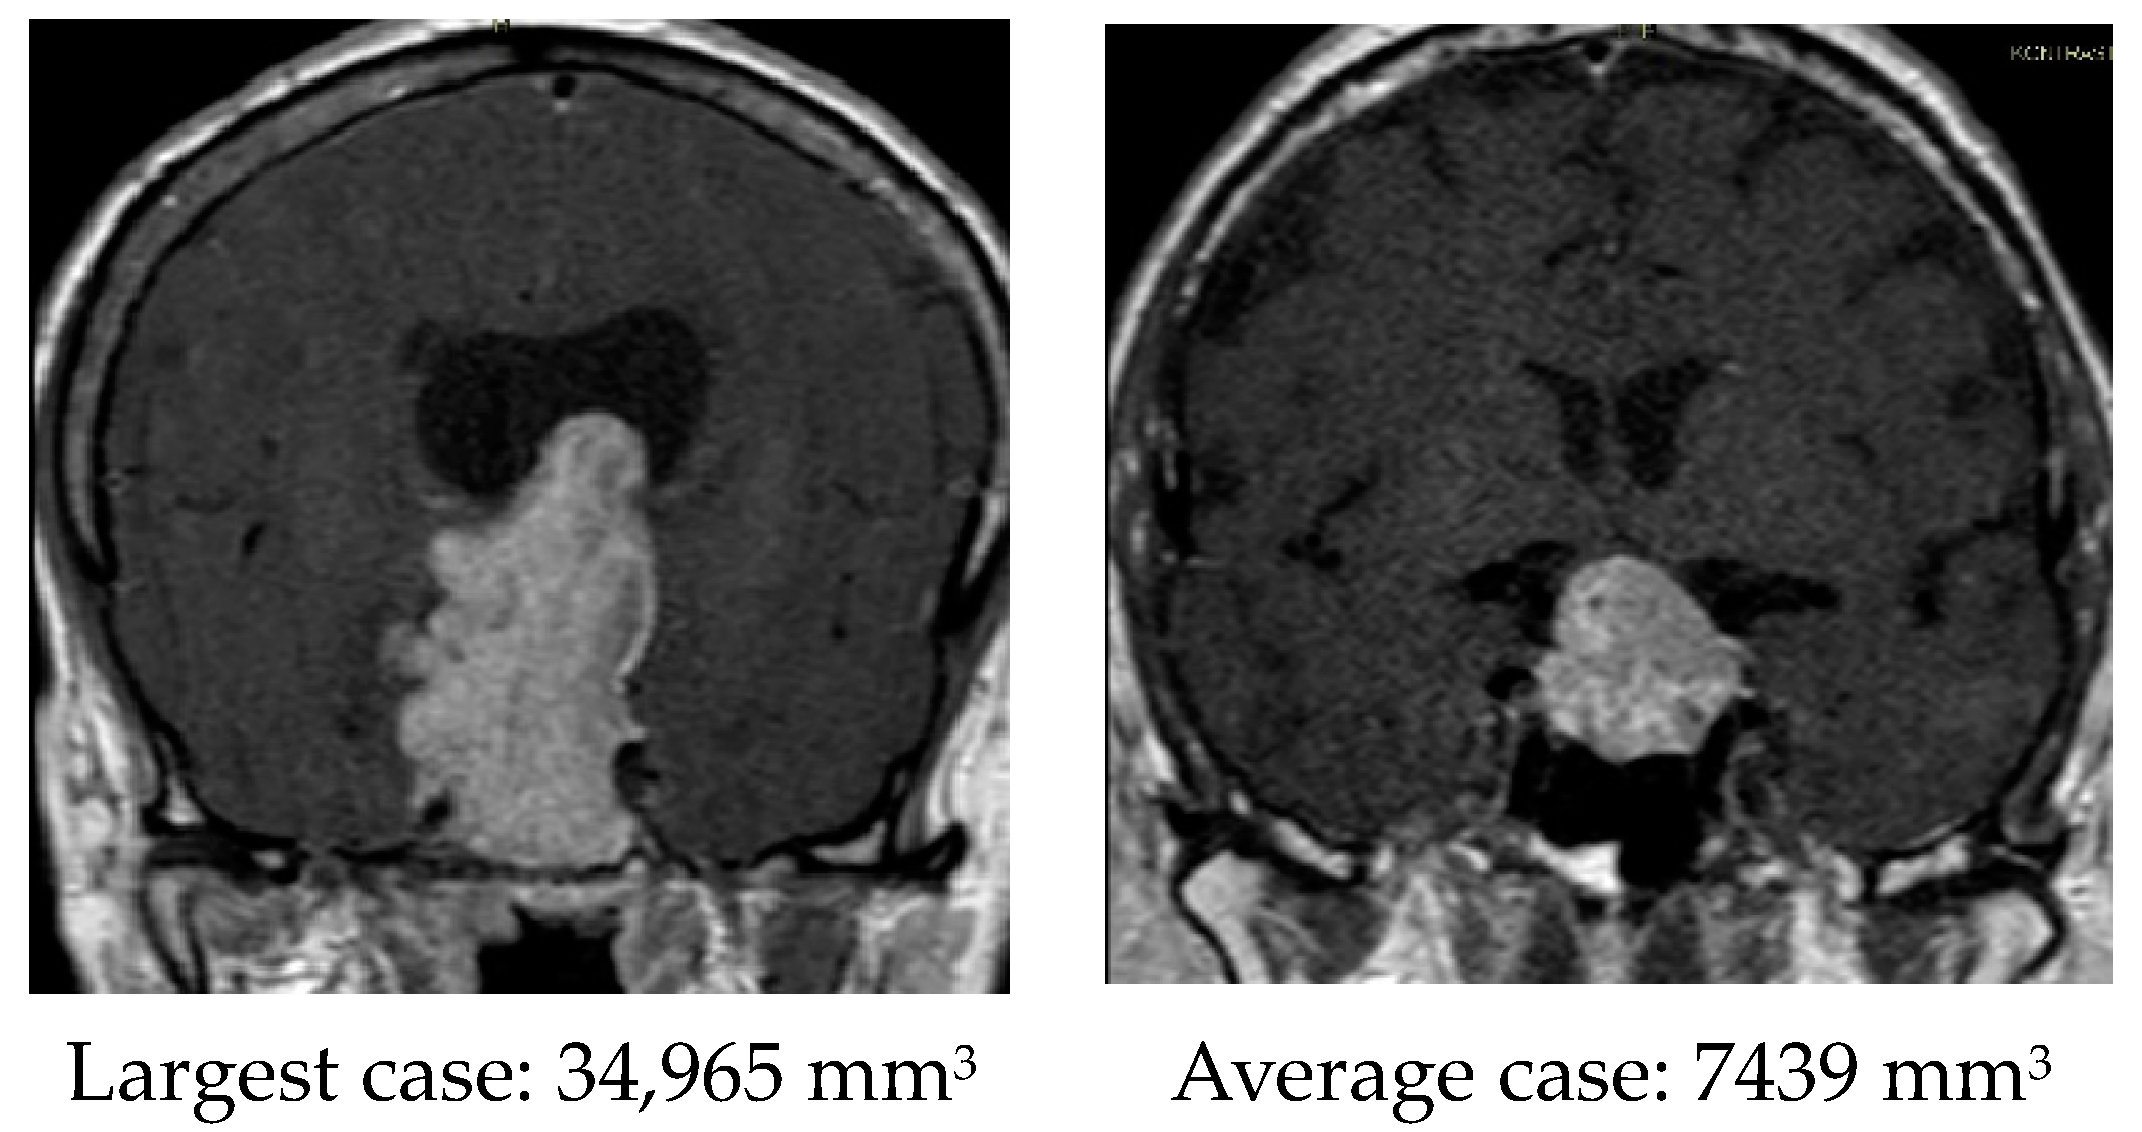

| Tumor size, mm3 | 7802 (2577–11,261) | 5130 (2344–6026) | 10,473 (3753–16,273) | 0.041 |